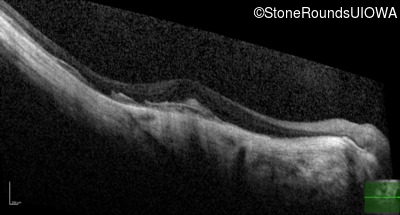

Optical Coherence Tomography - Right - 20/100 -2

Exemplar / OCT Stack